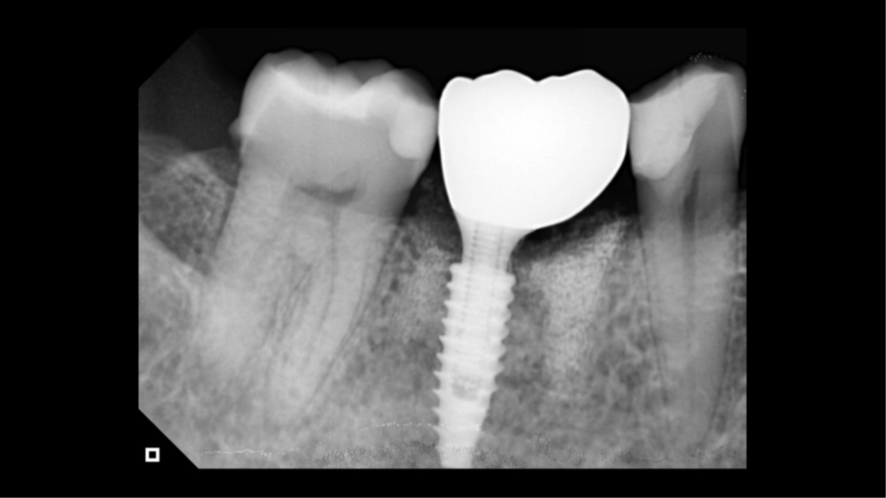

Agora, o laboratório de prótese consegue alinhar as malhas e fazendo a subtração da malha referente ao escaneamento do cicatrizador personalizado fora da boca, parafusado no análogo, temos exatamente o perfil de emergência adquirido pelo cicatrizador personalizado. Então, é realizado o CAD da coroa sobre implante (Figura 16), e após a fresagem em zircônia, acabamento, polimento e maquiagem, recebemos a coroa fresada em zircônia cimentada no pilar Base T (Figuras 17 e 18) pronta para ser instalada no implante. Logo após a instalação da coroa sobre implante (Figura 19), uma radiografia periapical foi realizada (Figura 20), a fim de confirmar a adaptação correta da coroa sobre implante.